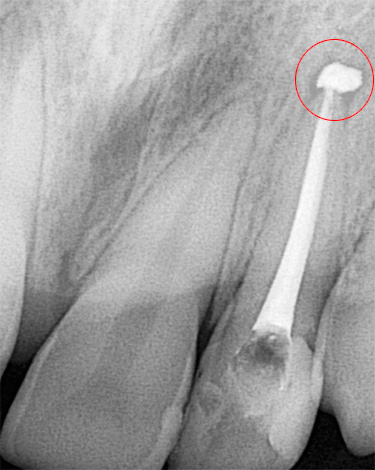

Instrumento quebrado no canal: se operado incorretamente com pequenos instrumentos endodônticos, é possível atolar o final da “agulha” com sua subsequente quebra, o que não permite curar qualitativamente a pulpite. Parte do canal não é processada e não é selada. Se os micróbios continuarem a se multiplicar nos espaços vazios da raiz, isso causará a dor da periodontite, indicando inflamação da raiz.

Remoção de um instrumento quebrado do canal do dente